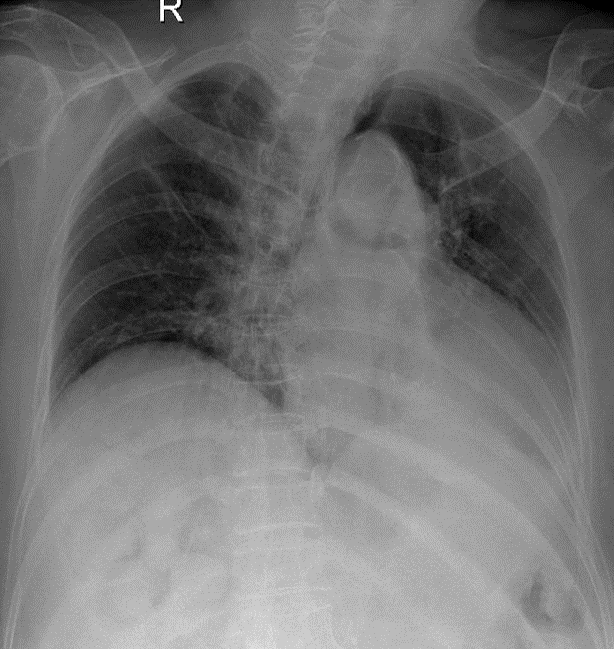

1-Khí quản lệch(T) 2-Góc carina dãn rộng 3-Xẹp thùy dưới phổi (T), kéo bóng tim và trung thất lệch(T) 4-Xơ rải rác phổi (P) 5-Cung động mạch chủ đóng vôi 6-Vẹo cột sống ngực sang (T)